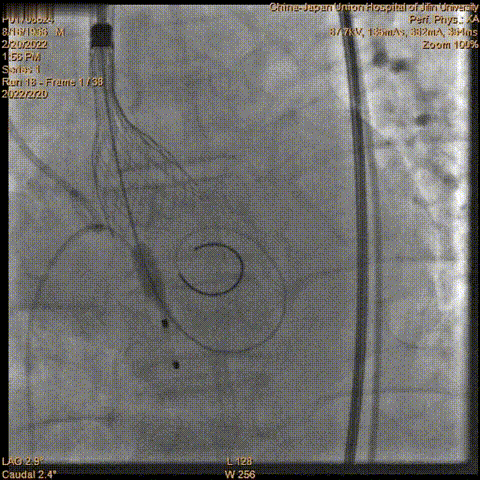

瓣膜释放

术中超声

超声结果示:微量瓣周漏,主动脉瓣口峰值流速为1.98 m/s,峰值跨瓣压差为 16 mmHg